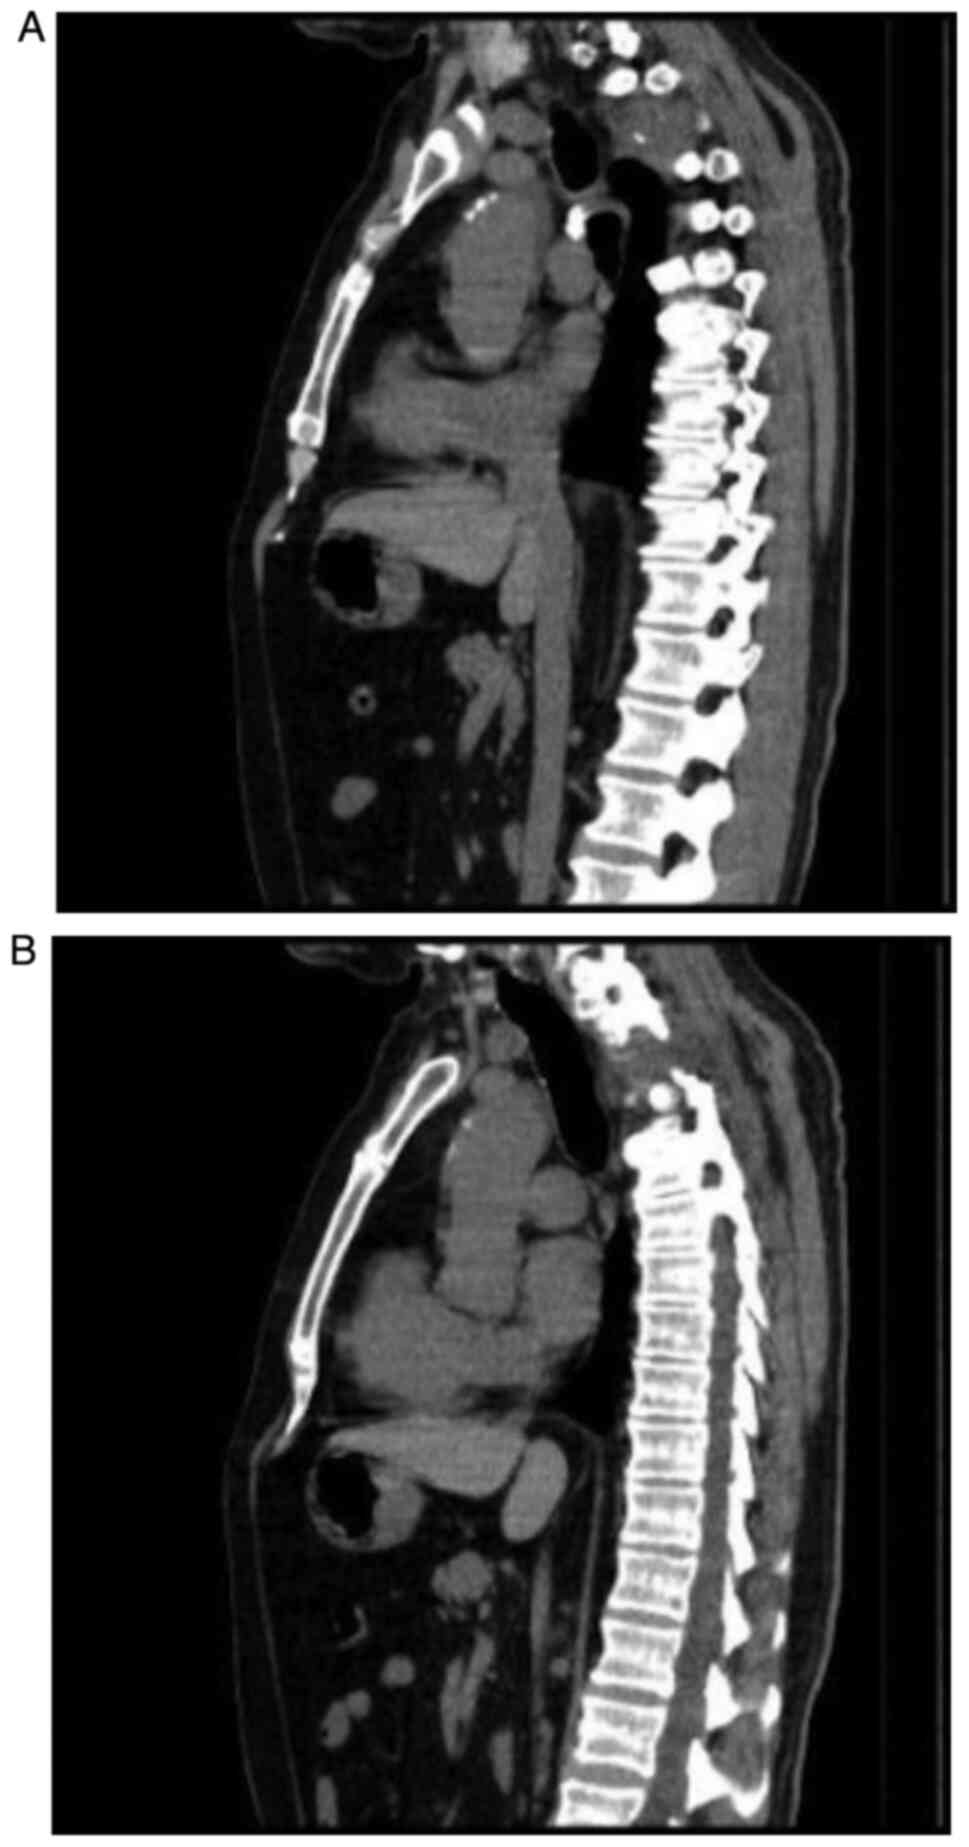

A new thoracic CT scan was performed in March 2018 which revealed a right apex lung tumor with spine involvement and mediastinal paratracheal ipsilateral adenopathies (Fig. 1A and B).

Figure 1

(A and B) Thoracic CT scan. Right lung apex tumor with spine involvement and mediastinal paratracheal ipsilateral adenopathies. CT, computerized tomography.